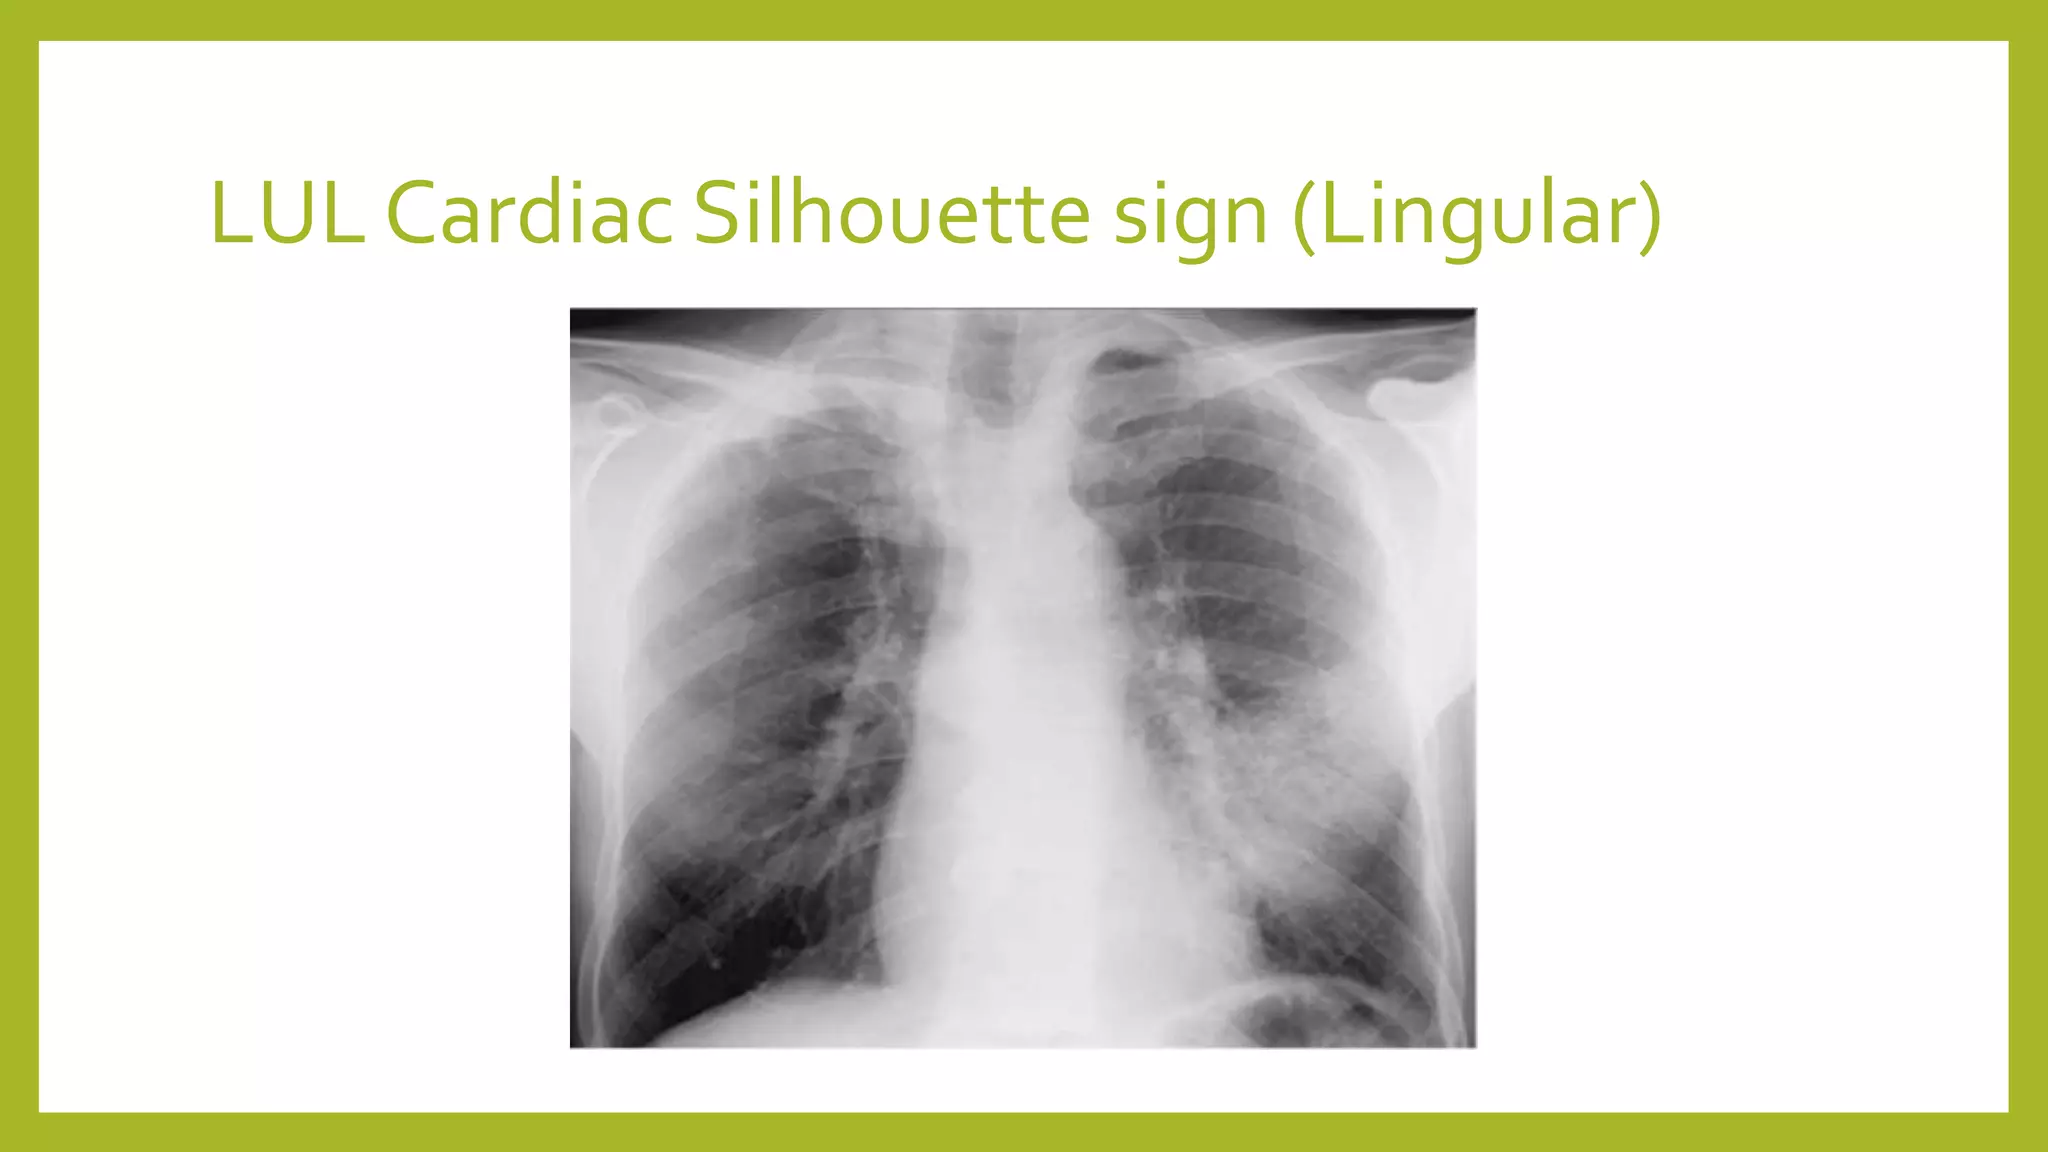

The document provides guidance on approaching and interpreting chest x-rays (CXR). It outlines steps to check the name, date and quality of the film, systematically scan the CXR looking for abnormalities, and determine if the lungs appear too white or black. Specific signs are described to help localize abnormalities, including the cardiac silhouette sign and pleural effusion signs. Examples are given of respiratory distress syndrome, tetralogy of fallot, transposition of great arteries, and total anomalous pulmonary venous return. The take home message is to summarize positive findings, compare to prior CXRs if available, and confirm findings with a radiologist.